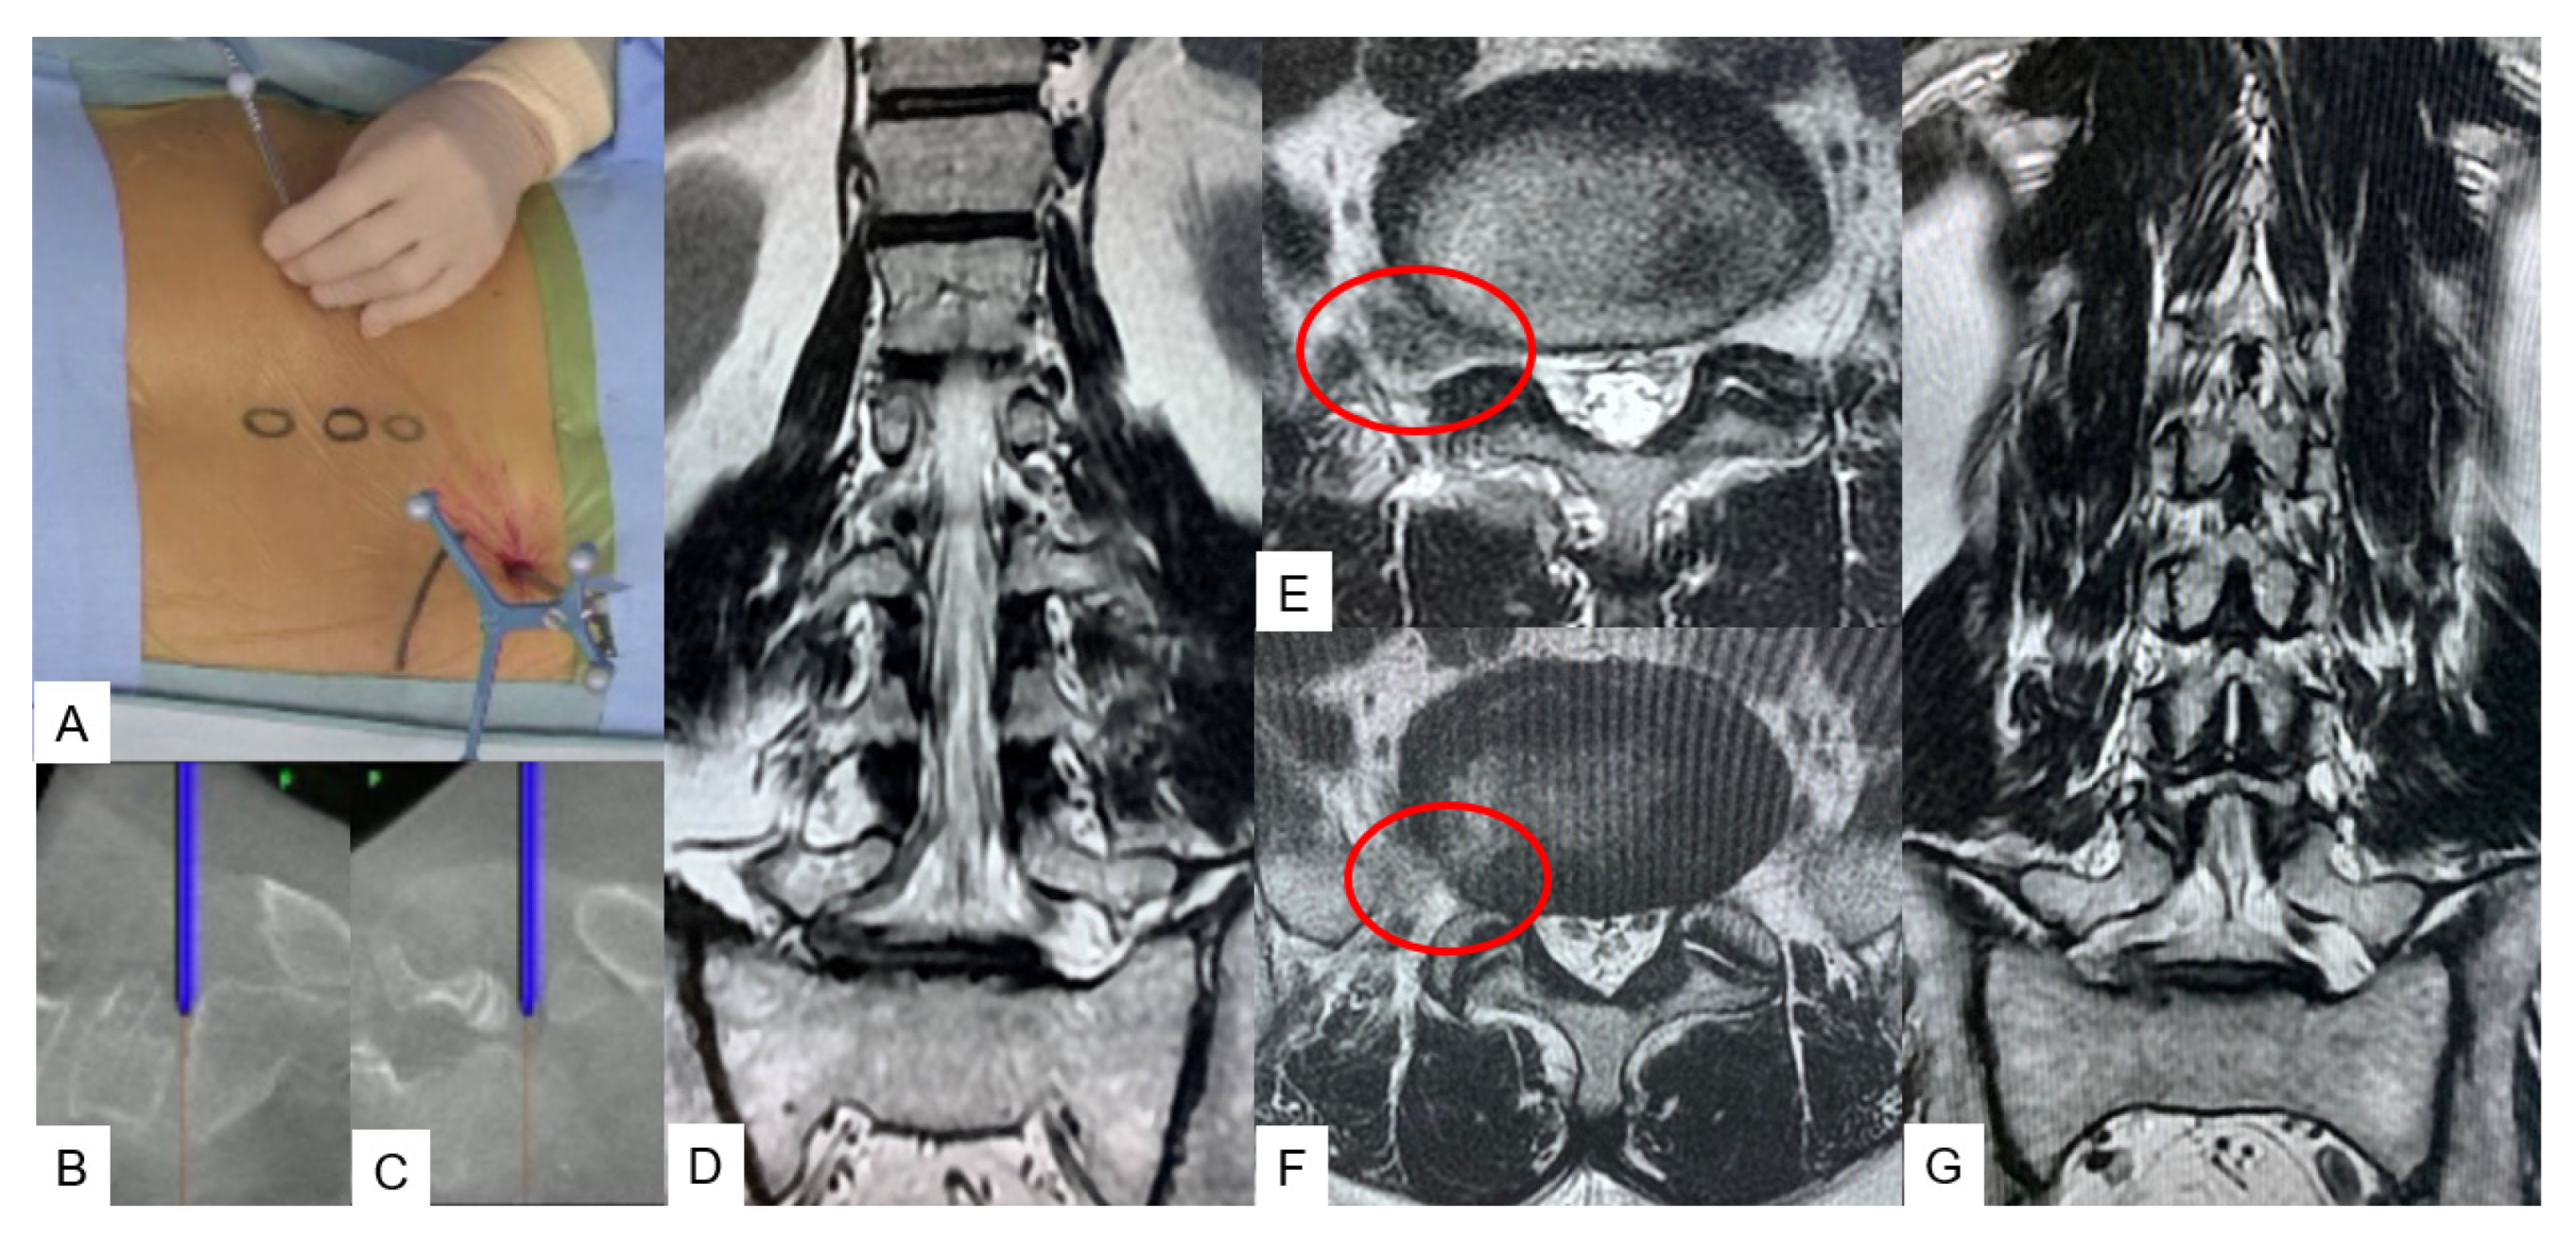

3.2.1. Adult Spinal Deformity [12]

3.2.2. C-Arm-Free Biopsy [13]